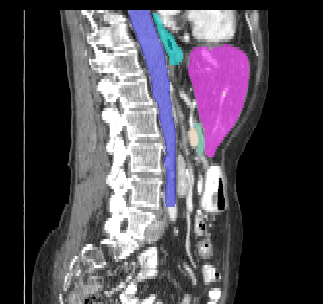

Recently, deep learning methods have achieved state-of-the-art performance in many medical image segmentation tasks. Many of these are based on convolutional neural networks (CNNs). For such methods, the encoder is the key part for global and local information extraction from input images; the extracted features are then passed to the decoder for predicting the segmentations. In contrast, several recent works show a superior performance with the use of transformers, which can better model long-range spatial dependencies and capture low-level details. However, transformer as sole encoder underperforms for some tasks where it cannot efficiently replace the convolution based encoder. In this paper, we propose a model with double encoders for 3D biomedical image segmentation. Our model is a U-shaped CNN augmented with an independent transformer encoder. We fuse the information from the convolutional encoder and the transformer, and pass it to the decoder to obtain the results. We evaluate our methods on three public datasets from three different challenges: BTCV, MoDA and Decathlon. Compared to the state-of-the-art models with and without transformers on each task, our proposed method obtains higher Dice scores across the board.